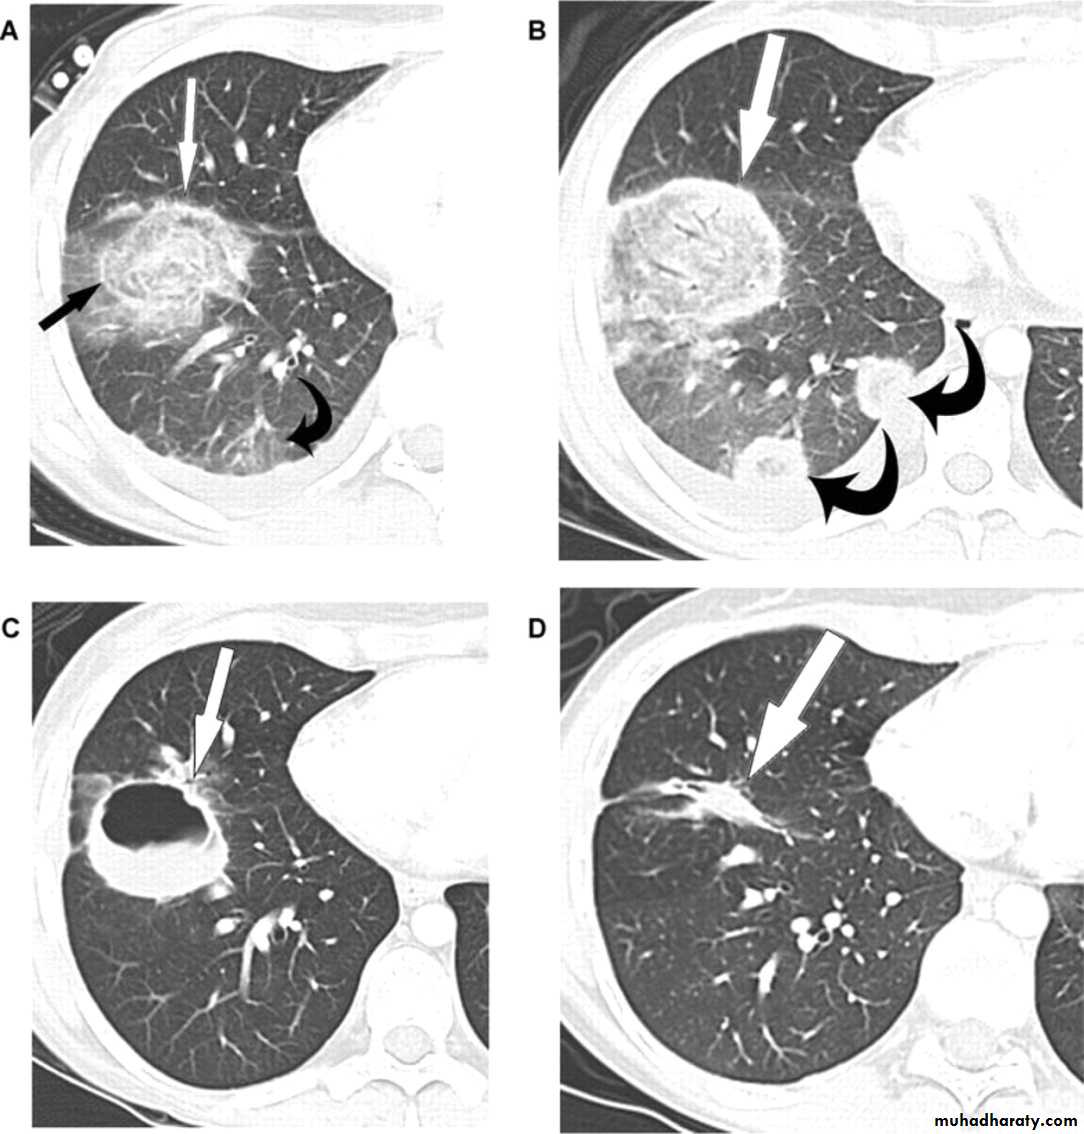

Aspergillus lung infectionDr.Mustafa Nema/Baghdad College of Medicine 2014